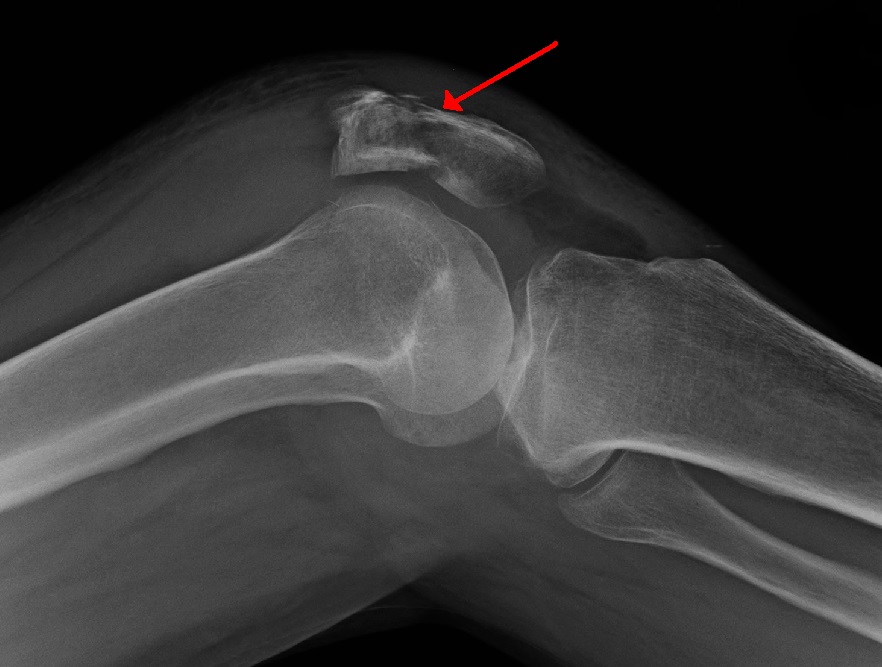

Patellar fracture Image Knee Fracture X Ray Ct scans are used to further. learn how to perform and interpret knee radiographs for various indications and pathologies. avulsion fractures of the knee are numerous due to the many ligaments and tendons inserting around this joint. symptoms of a knee fracture include pain, swelling, and bruising at the site of injury; learn about the causes,. Knee Fracture X Ray.